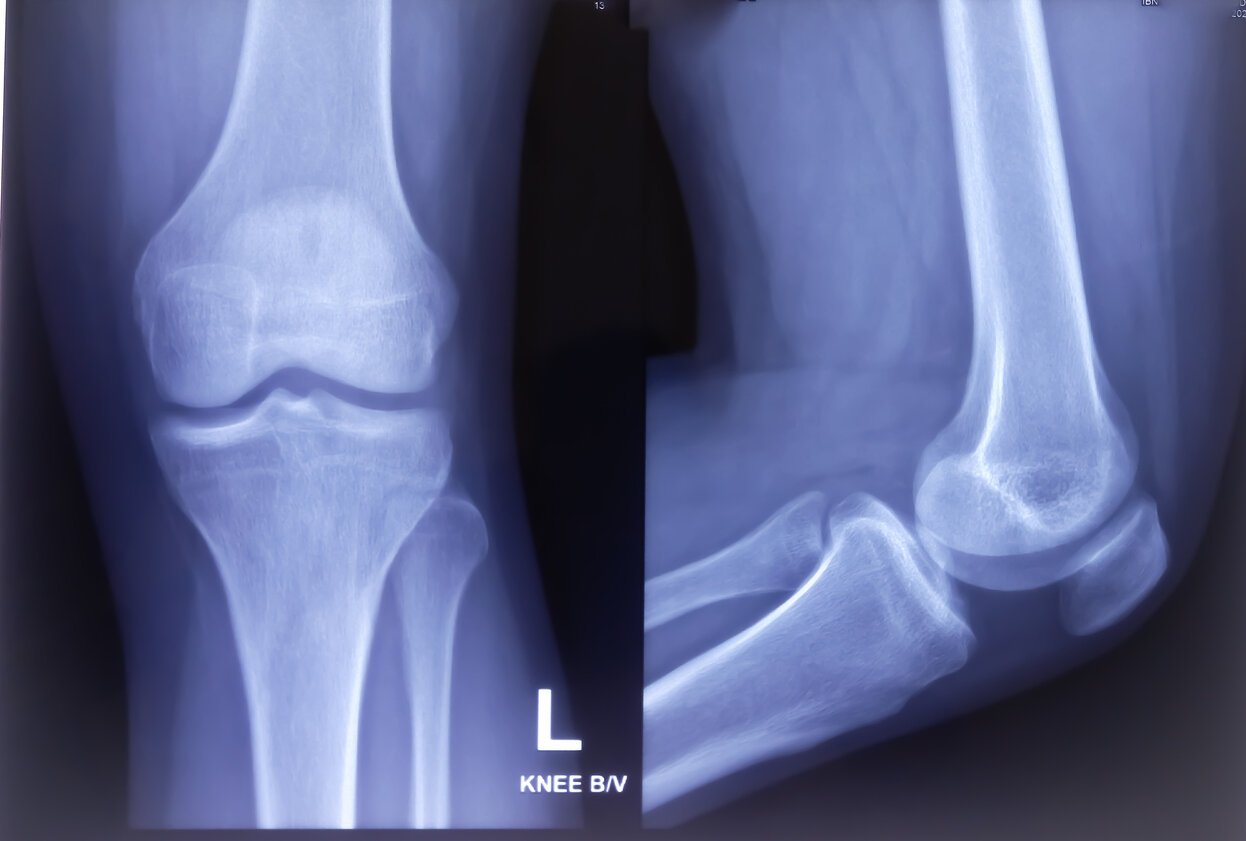

x-ray of knee joint both view normal knee joint

Les traitements médicamenteux (antalgiques, anti-inflammatoires non stéroïdiens) ou les infiltrations (acide hyaluronique, PRP) ne sont pas toujours efficaces et ne restaurant par l’articulation lésée. Dans ces conditions, pouvoir prédire des années en avance que l’on va développer une arthrose changerait considérablement le quotidien des futurs arthrosiques, en particulier des femmes, qui sont à 60% les plus touchées par cette maladie. D’autant qu’aujourd’hui, seule l’imagerie (dans la plupart des cas, la radio) peut permettre de poser un diagnostic, et jamais de façon précoce.